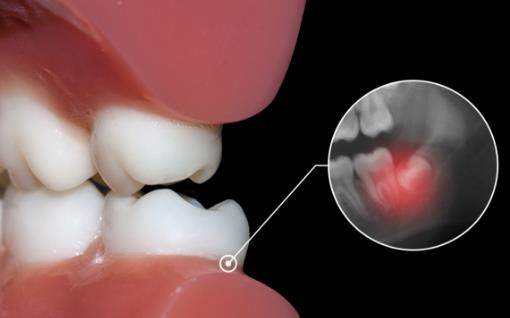

2.侵犯邻牙:通常患者不自知,而由牙医以X光诊断得知。通常智齿萌发的空间不足,而会倒在第二大臼齿上,因而造成第二大臼齿清洁不易,甚至是牙齿部分吸收的现象,造成患者不舒适或牙疼。

6.阻生齿:通常这是最讨厌的一种,牙医会觉得很难搞定,但病人却不一定有感觉,因此忽略了。这一种类型的牙齿,通常埋在齿槽骨的里面,如果会痛,或是诊断会有病灶发生的时候,就需要拔除了。